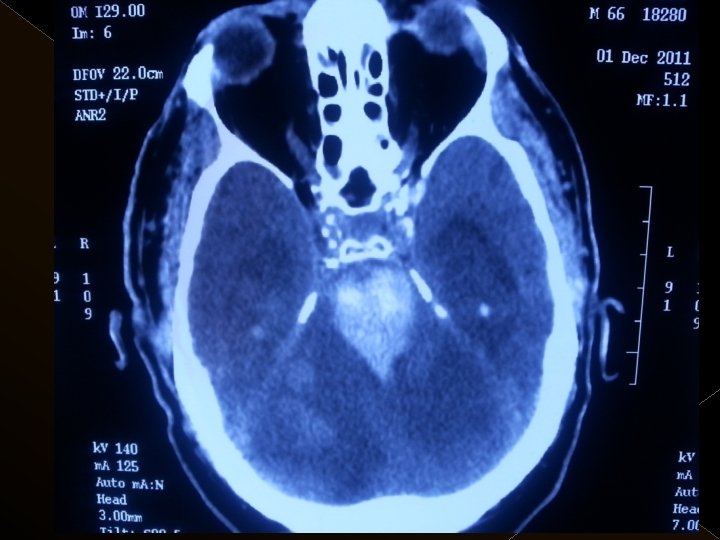

Görüntüleme İşlem öncesi § Bazal kontrastsız BT § BT anjiografi (varsa perfüzyon BT ) § MR (DW, ADC) İşlem sonrası § MR ( DW, ADC, SWI) § 24. saatte kontrol BT veya MR

KOMPLİKASYONLAR Ponksiyon bölgesi komplikasyonları � Trombektomi stentine ait komplikasyon (*1) � Diseksiyon(*2) � Karotikokavernöz fistül (‘ 1) � Hemorajik komplikasyonlar(‘ 5) Semptomatik-nonsemptomatik � İskemik komplikasyonlar (3) � Reoklüzyon (2 i. a) � Kontrast madde nefropatisi �